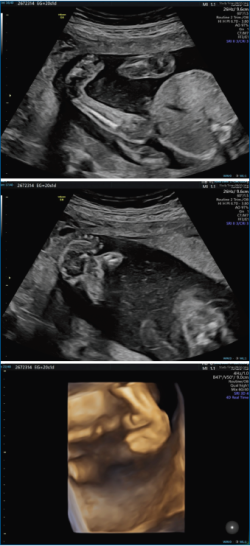

El pie zambo se puede detectar por ecografía a partir de la semana 12 de gestación (Figura 1). Los primeros informes de imágenes prenatales del pie zambo mediante ultrasonido aparecieron en 1985(8). Desde entonces, la detección del pie zambo mediante ecografía ha mejorado drásticamente en las últimas dos décadas, aunque los diagnósticos falsos positivos siguen siendo elevados, con valores que oscilan entre el 10 y el 40%(8,9,10).

Brasseur et al. describen un análisis sistemático del pie fetal en 3 planos. En el corte sagital de la pierna, incluyendo la tibia, cuando hay posición constante del pie en flexión plantar (equino), lo más probable es que se trate de un pie zambo. Si es normal, podría descartar el diagnóstico de pie zambo. Si el corte sagital es normal y uno de los otros cortes no lo es, lo más probable es que se trate de una deformidad posicional del pie. Si el corte coronal es el único corte anormal y muestra supinación del pie, sugiere el diagnóstico de pie supinado. Si el corte transversal es el único corte anormal y muestra aducción del antepié, sugiere el diagnóstico de metatarso aducto(10).

Es importante tener en cuenta que la gravedad del pie zambo no se puede determinar mediante un examen ecográfico. Solo se puede determinar mediante un examen clínico del pie.